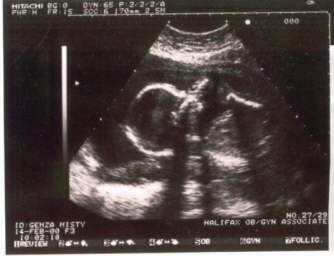

Our first glimpses at our new baby were black and white, grainy, and hard to make out but even then we knew she was going to be beautiful.

Our first look at Madison 5 weeks (10/99).